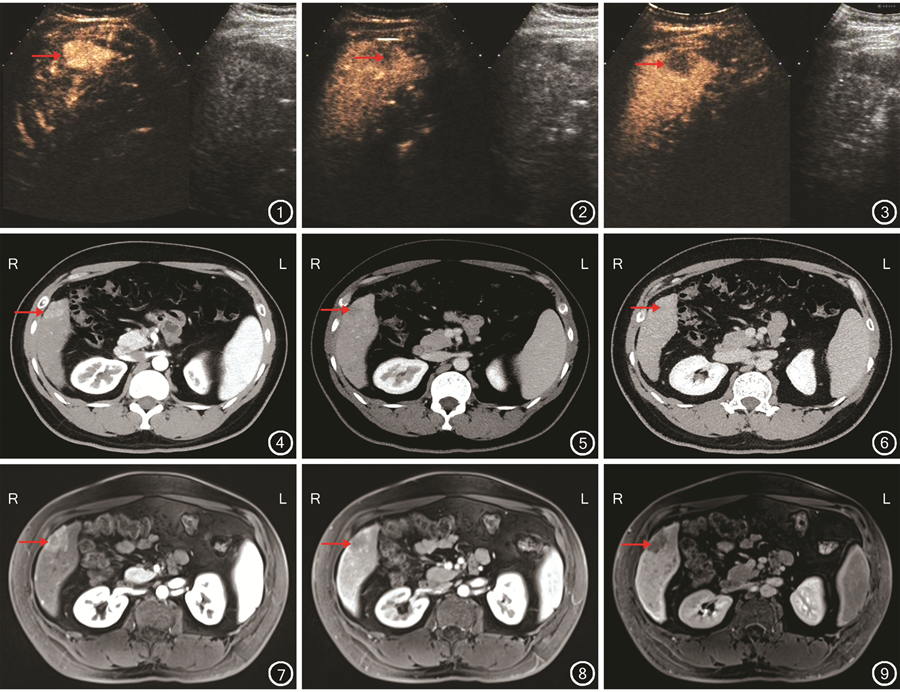

小肝癌超声造影、增强CT、增强MRI检查不同时期强化方式分布见图1, 2, 3, 4, 5, 6, 7, 8, 9。

153个超声造影检查检出小肝癌病灶中,表现为“快进快出”强化方式140个,“快进慢出”强化方式12个,“等-低-低”强化方式1个。

154个增强CT检查检出小肝癌病灶中,表现为“快进快出”强化方式112个,“快进慢出”强化方式13个,“等-低-低”强化方式14个,“环状高-低-低”“低-低-低”强化方式各5个,“高-高-高”强化方式3个,“等-等-等”“等-等-低”强化方式各1个。

154个增强MRI检查检出小肝癌病灶中,表现为“快进快出”强化方式134个,“快进慢出”强化方式1个,“等-低-低”强化方式8个,“环状高-低-低”强化方式5个,“持续性环状高”强化方式2个,“高-高-高”“低-低-低”“等-等-低”“边缘延迟强化”强化方式各1个。

肝细胞癌发生、发展过程中,门静脉及正常肝动脉减少甚至消失,同时异常新生动脉增多[16]。已有的研究结果显示:肝细胞癌的主要供血动脉常因伴有动、静脉短路而表现为富血供型,影像学检查动脉期造影剂快速进入肿瘤呈高增强,门静脉期或延迟期呈快速消退,整体表现为“快进快出”强化方式[17]。本研究结果显示:153个超声造影检查检出小肝癌病灶中,140个病灶表现为“快进快出”强化方式,且动脉期高强化数目为152个;超声造影检查小肝癌病灶动脉期高强化数目均高于增强CT和增强MRI检查,与既往研究结果一致[18, 19]。笔者分析:超声造影检查扫描特点为实时动态观察,而增强CT、增强MRI检查为固定时间点扫描观查,可能错过病灶的短暂性强化表现[18,20]。此外,有研究结果显示:与增强CT或增强MRI检查比较,超声造影检查对微泡造影剂具有更好的灵敏度[21]。

超声造影、增强CT、增强MRI检查可反映病灶供血血管的变化[22]。有研究结果显示:“快进快出”强化方式在肝细胞癌中仅占69.3%[23]。本研究结果显示:超声造影、增强CT、增强MRI检查小肝癌病灶表现为“快进慢出”强化方式分别为12、13、1个。有文献报道:肝细胞癌早期,病灶由于缺乏新生血管而以门静脉供血为主,造影剂从门静脉进入病灶可能是产生“快进慢出”强化方式的原因[24]。Jang等[25]的研究结果显示:50%的高分化肝细胞癌超声造影检查时不出现廓清。Boozari等[26]的研究结果显示:94.4%的高分化肝细胞癌超声造影检查延迟期可表现高或等增强。本研究结果显示:超声造影、增强CT、增强MRI检查小肝癌延迟期,病灶均有高或等增强分布。因此,对于超声造影检查延迟期不出现廓清的高危患者,需引起重视[27]。